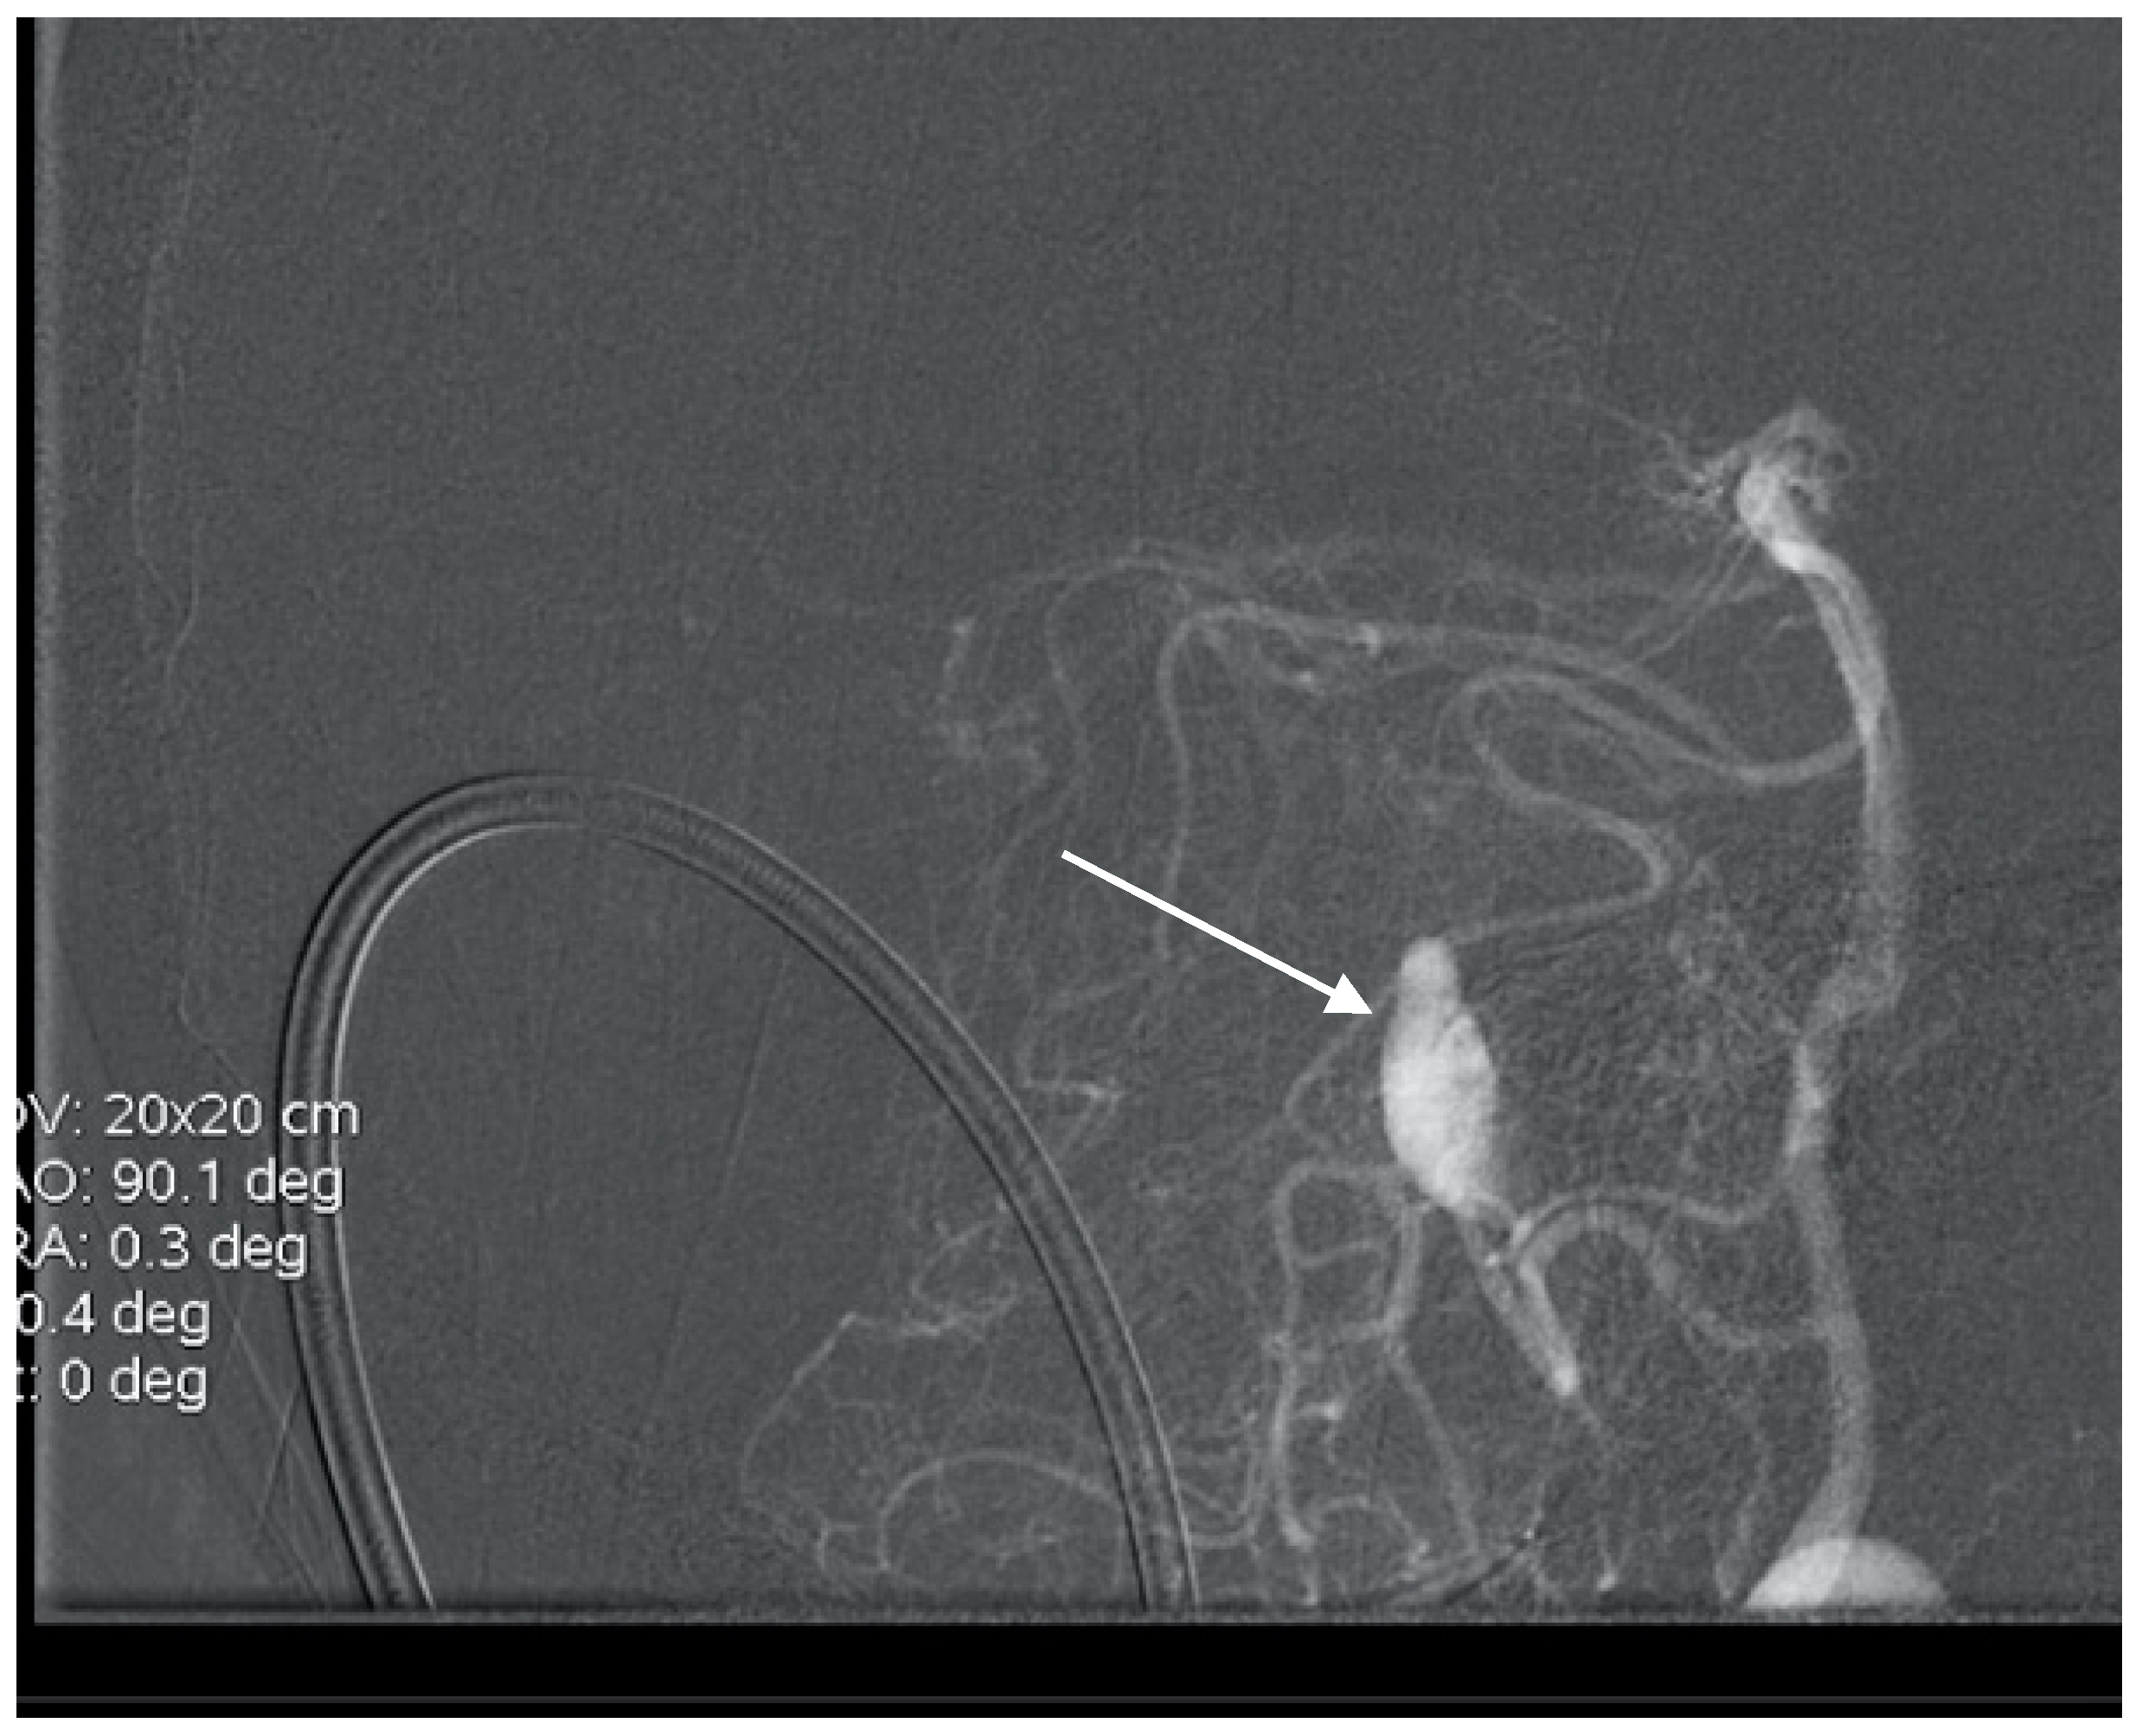

Figure 10. Angiogram showing embolization of the AVM (short arrow) and coiling of the aneurysm (long arrow).

2.6. SCA Aneurysms and AVM

A 58-year-old woman with sudden onset of headache and vomiting was admitted to hospital. The CT scan showed subarachnoid hemorrhage (Fischer grade 3), and the CT angiogram revealed AVM with an associated aneurysm on the left superior cerebellar artery (Figure 9). Endovascular treatment was indicated, and successful Onyx embolization of AVM and coil embolization of the aneurysm was performed (Figure 10). The postoperative course was also without complication, and the patient is followed up.